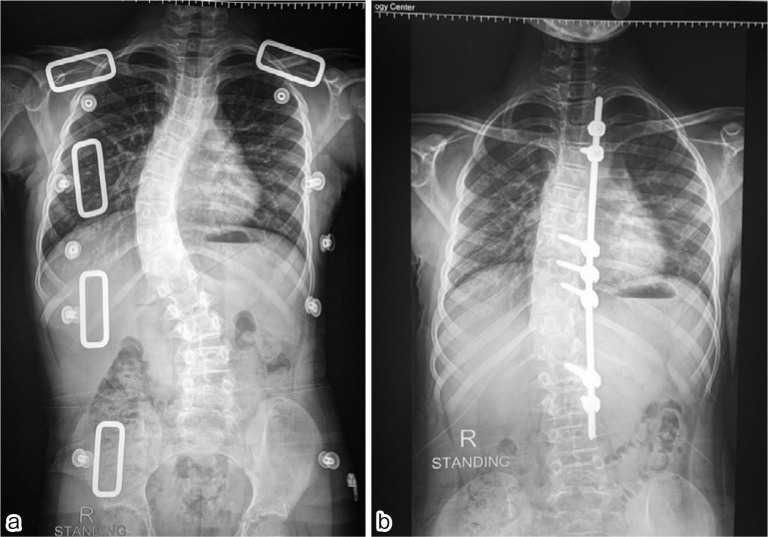

Background: Distraction-founded techniques such as traditionally growing rods or magnetically controlled growing rods are the almost globally accepted management patterns for early onset scoliosis. However, periodic lengthening operations are still needed. Moreover, an MCGR is difficult to contour, and implant-associated problems are common. We developed concave side apical control of the growing rod in which an additional anchor site is inserted at the apex to enhance stability and assist in the adjustment of axial deformity.

Methods: Entirely skeletally immature early onset scoliosis (EOS) cases with a progressive curve of >40° and without bone or soft tissue weakness were appropriate for this study. Coronal Cobb angle, sagittal parameters, complications, spinal length, and reoperations were documented with at least a 3-year follow-up.

Results: In this study, 15 patients were involved. The mean age was 7 years. The mean preoperative Cobb angle was 48°, which postoperatively became 12° with the percentage of coronal correction reaching 75.73%. The mean Cobb angle degrees of correction were 39°. T1-S1 height increased by 10 mm/year. Postoperative complications occurred in two cases with single rod technique and rod breakage.